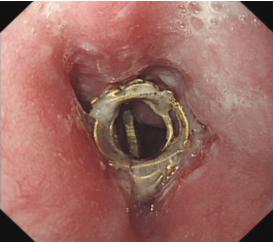

内镜下食管异物取出